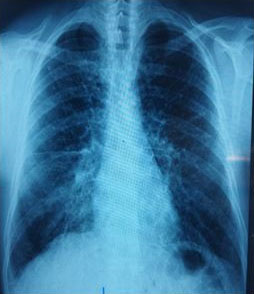

Case Report: We present a female with right perinephric abscess and reno-duodenal fistula secondary to a long-standing history of kidney stones. Treatment involved drainage of the abscess, nephrostomy tube placement, intravenous antibiotics, and open nephrectomy and duodenal repair with gastrojejunostomy.

Conclusion: In this report, we discuss management strategies which range from conservative treatment of antibiotics to open nephrectomy. In addition, we will discuss the urologic and gastroenterological post-operative complications in this patient.